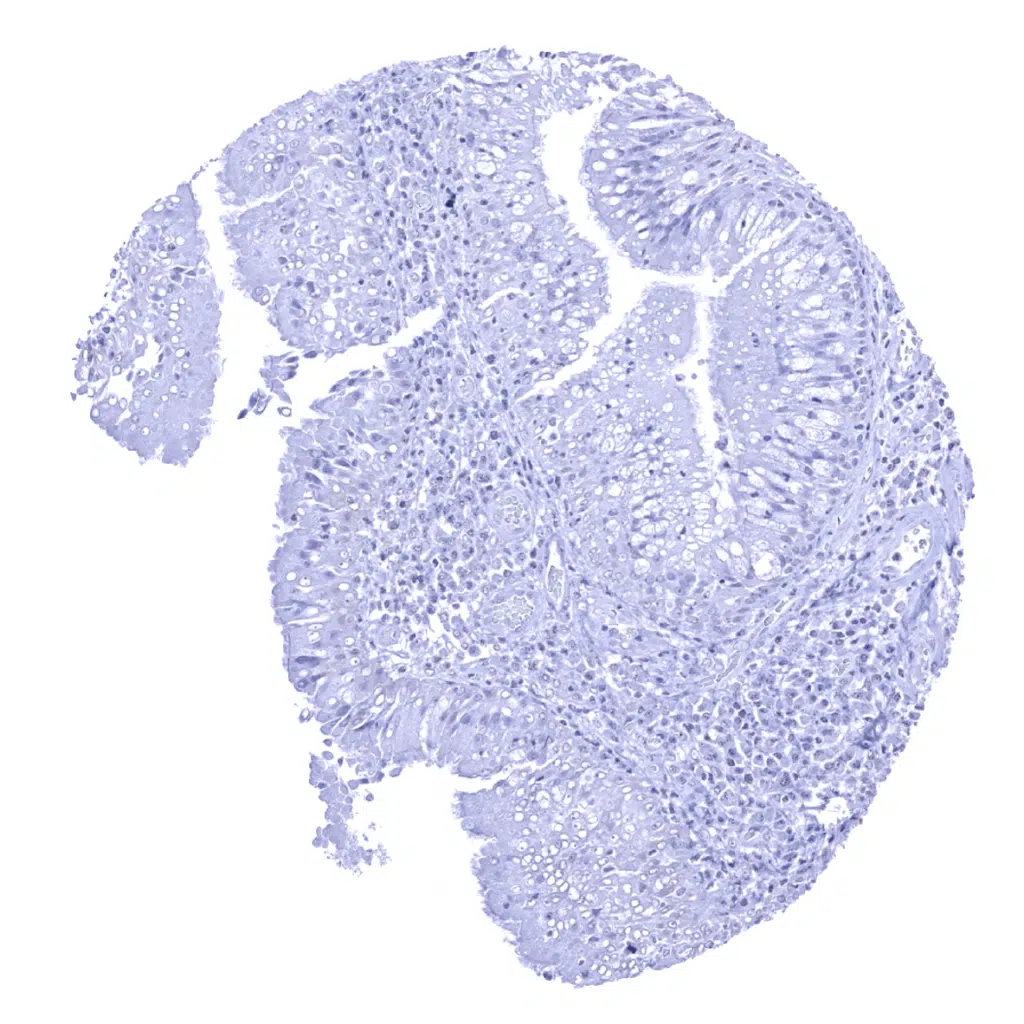

Appendix, mucosa

Appendix, muscular wall